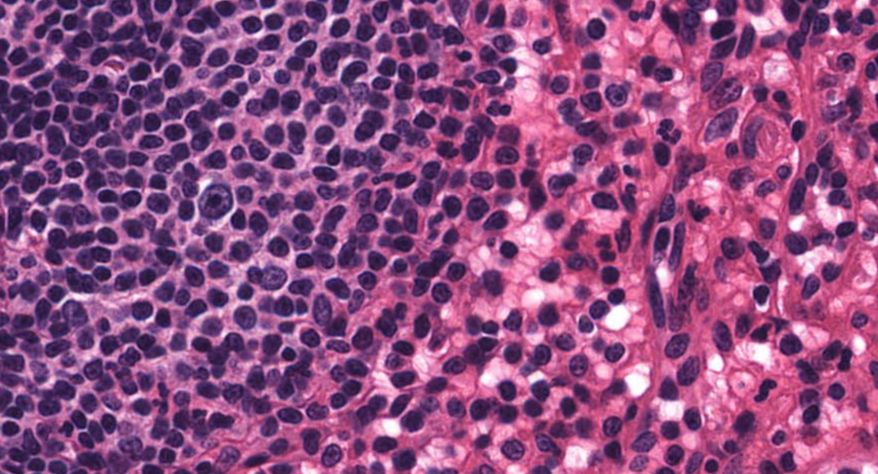

低倍镜:胸腺表面包有薄层结缔组织构成的被膜,结缔组织深入实质,将胸腺分成许多不完整的小叶。每个小叶分为周围的皮质和中央的髓质两部分。皮质中胸腺细胞排列密集,故染色深;髓质中胸腺细胞较少,胸腺上皮细胞多,故染色浅,其中可见染成红色的圆形小体-胸腺小体。高倍镜:胸腺小体大小不等,由几层至十几层扁平的胸腺上皮细胞呈同心圆状排列而成,其外周的细胞较幼稚,细胞核明显;小体中央部分的上皮细胞已退化,细胞核消失,胞质呈均质状,染成红色。